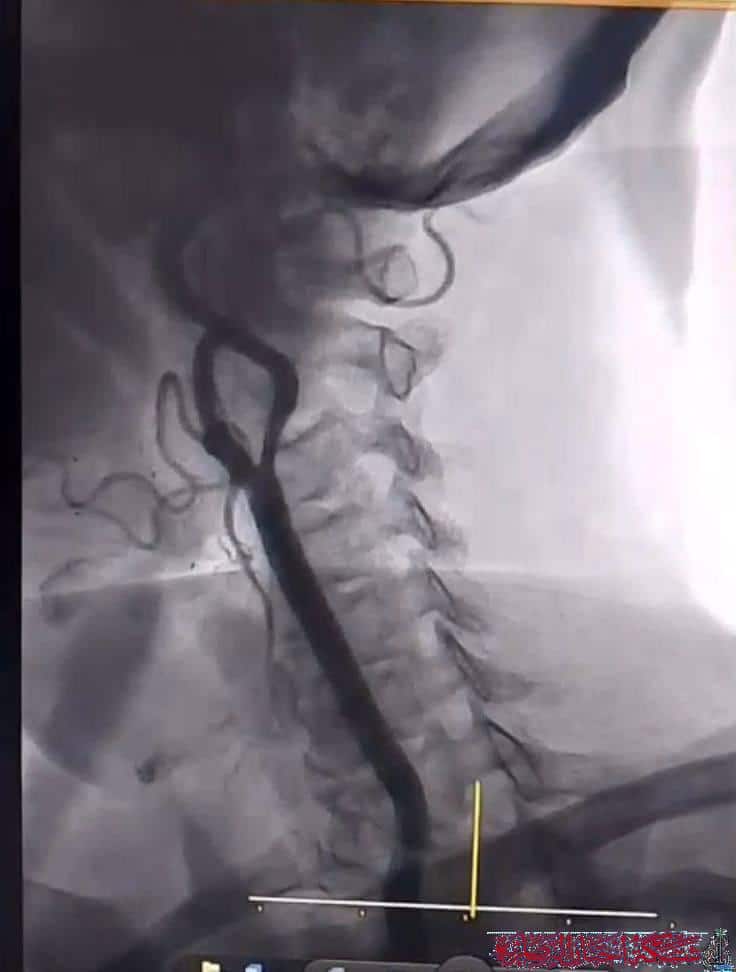

وأوضح عبد الهادي لشبكة اخبار الناصرية أن العملية الأولى تمثلت في فتح الشريان الفخذي الأيمن وزرع شبكة نفّذها بنجاح الدكتور عزّت المياحي، فيما شهدت العملية الثانية إجراء قسطرة لشرايين الدماغ على يد الدكتور إسماعيل السوز، وهو إجراء يُعد من أكثر العمليات تعقيدا ودقة.